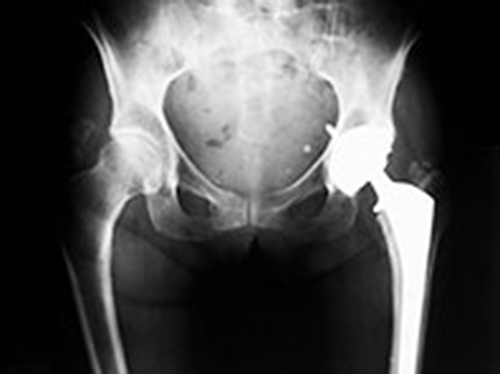

Группа специалистов разработала новые метаматериалы, которые могут решить проблемы плохо протезов (подходящих в области суставов), контактного дерматита и сальных кист у пациентов с ампутированными конечностями, пишет Zee News. Метаматериалы - это синтетические композитные материалы со структурой и свойствами, которых лишены природные материалы. К примеру, их можно запрограммировать таким образом, чтобы те деформировались особым образом.